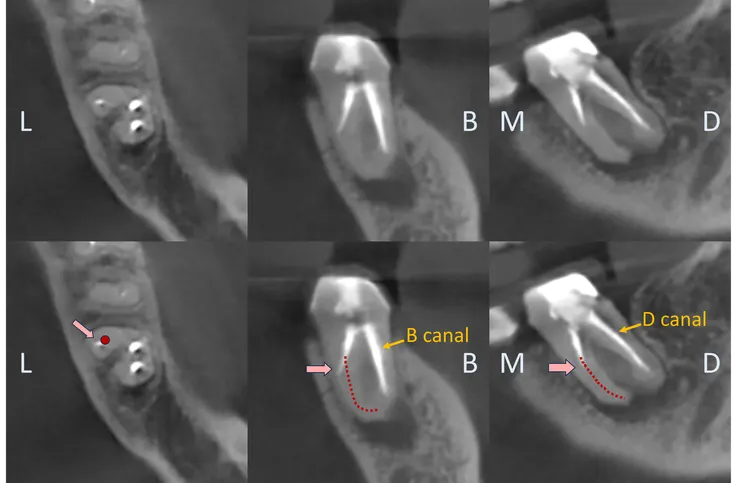

果然,從 CBCT 才能看清真相!

(因為 B & D canal 的關鍵點太深了拍不到,因此本篇只 focus 在 ML canal.)

不光是 PA film, 在 CBCT 上我們也可以依據 root form 推測出 canal 的走向 (如下排圖中的紅色標示處)。於是我們可以清楚地看出,先前的路徑 (粉紅色箭頭標示處) 明顯地往 lingual & mesial 偏移,並勘勘在 perforation 前停住......

所以真正的路徑應該會是在舊充填的 DB side.